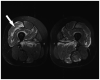

Figure 5-4.

Polymyositis. Muscle biopsy demonstrates endomysial mononuclear inflammatory cell infiltrate surrounding and invading non-necrotic muscle fibers (modified Gomori one-step trichrome stain).

Figure 5-5.

Inclusion body myositis. Skeletal muscle MRI scan of thighs reveals atrophy of muscles and fibrofatty replacement, particularly affecting the vastus lateralis (VL) and vastus medialis (VM) muscles (arrows) with relative sparing of the rectus femoris muscle in between.